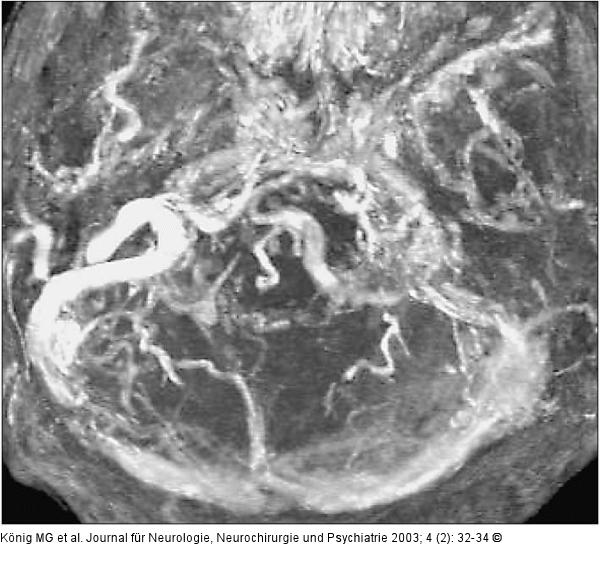

Abbildung 5: Sinus sigmoideus - Rekanalisation

Rekanalisation des Sinus Sigmoideus |